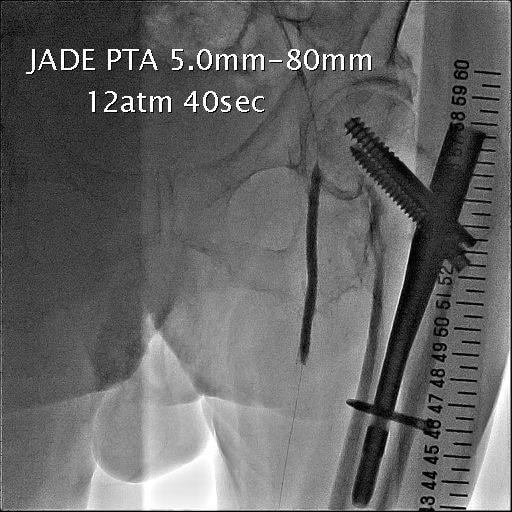

図4.SFA poba

SFAの狭窄部をcuttingバルーンにて拡張。